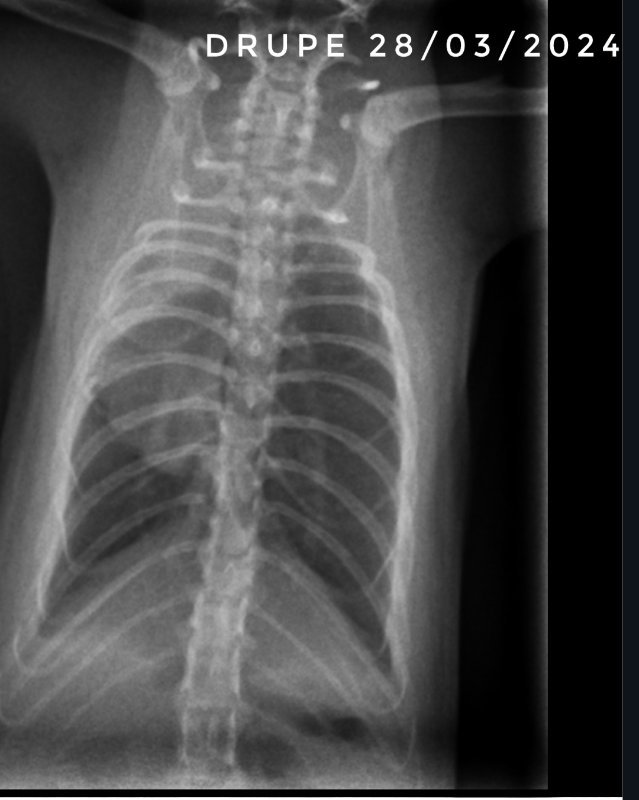

Les radios du jour.

Drupe a encore une belle évolution, on espère qu'à la prochaine consultation, dans 2 semaines 1/2, on pourra arrêter les médocs.

Les radios de Caryopse montrent une petite évolution positive en 1 semaine, donc on continue le chloramphenicol mais on arrête les nebu, ça le fait partir en détresse respiratoire régulièrement (3 fois en 1 semaine). Il a en plus un petit ulcère a l'œil gauche depuis jeudi dernier mais ça, ça guérit bien.